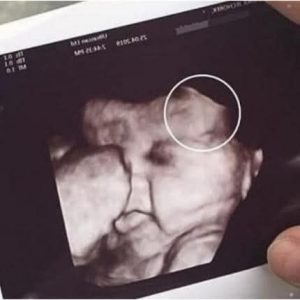

DONALD TRUMP ANNOUNCES TRUMP’S PREGNANCY!

During a high-profile appearance at the Detroit Economic Club in Michigan, Donald Trump shifted from his usual campaign messaging to share a personal family update. Speaking to an audience of…